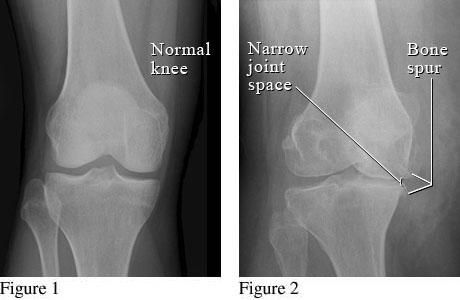

Οστεοαρθρίτιδα ονομάζεται η κατάσταση κατά την οποία η άρθρωση καταστρέφεται, λόγω εκφύλισης του αρθρικού χόνδρου. Η πάθηση συμβαίνει πιο συχνά σε ηλικιωμένους, υπέρβαρους και σε ανθρώπους που έχουν υποστεί σοβαρό τραυματισμό στη συγκεκριμένη άρθρωση, ωστόσο δεν έχουν διευκρινιστεί οι αιτίες που την προκαλούν. Ορισμένες φορές, η οστεοαρθρίτιδα γόνατος παρουσιάζεται ως συνέπεια άλλων νόσων που προσβάλλουν τις αρθρώσεις, όπως ρευματοειδής αρθρίτιδα, αγκυλοποιητική σπονδυλίτιδα, ψωριασική αρθρίτιδα κ.λπ.

Οστεοαρθρίτιδα γόνατος